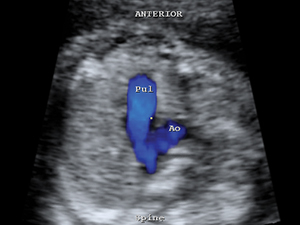

肺動脈與主動脈血流